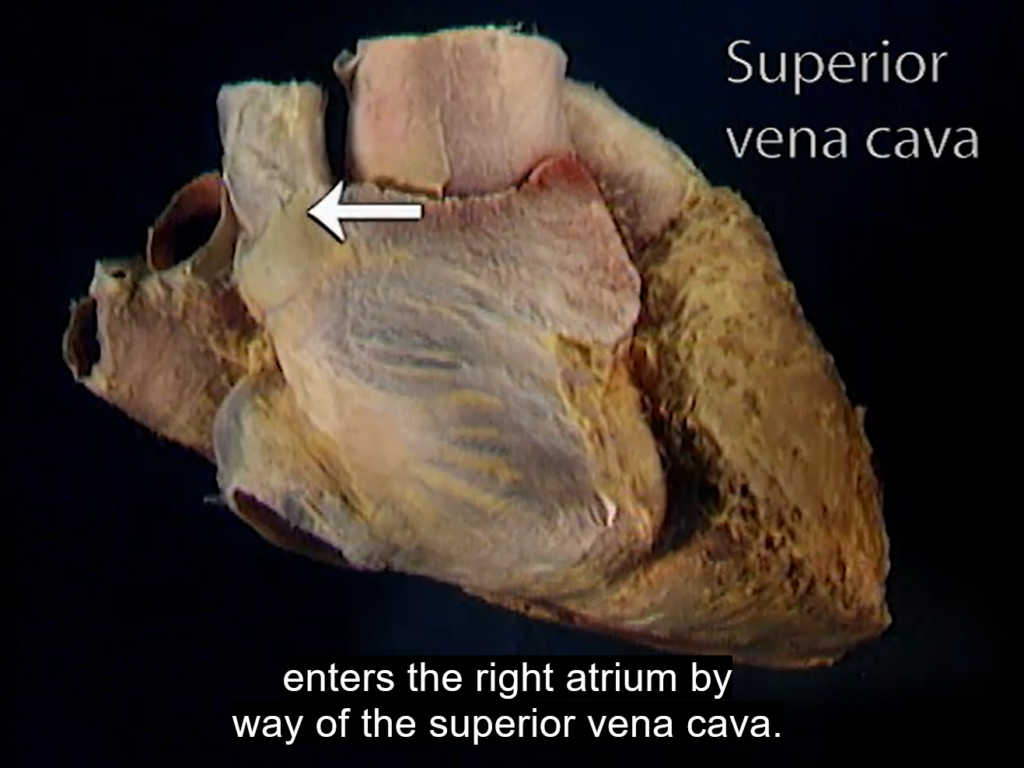

Dwa nowoczesne narzędzia online – Interaktywny Atlas Histologiczny oraz Wirtualny Atlas Anatomii Człowieka (Acland’s Video Atlas of Human Anatomy) – oferują bazę wysokiej jakości obrazów statycznych oraz materiałów wideo do nauki i zrozumienia mikroskopowych oraz makroskopowych struktur ludzkiego ciała.

Materiały Wirtualnego Atlasu Anatomii Człowieka (Acland’s Video Atlas of Human Anatomy) pokazują rzeczywiste tkanki i narządy w trójwymiarowej przestrzeni.

Kolekcję filmów można przeszukiwać według kategorii odpowiadającej anatomicznym częściom ciała oraz według alfabetycznie ułożonej listy nazw narządów i układów:

- narządy wewnętrzne klatki piersiowej i jamy brzusznej oraz układ rozrodczy.

Źródło zdjęć: Ackland’s Video Atlas of Human Anatomy; Interaktywny Atlas Histologiczny